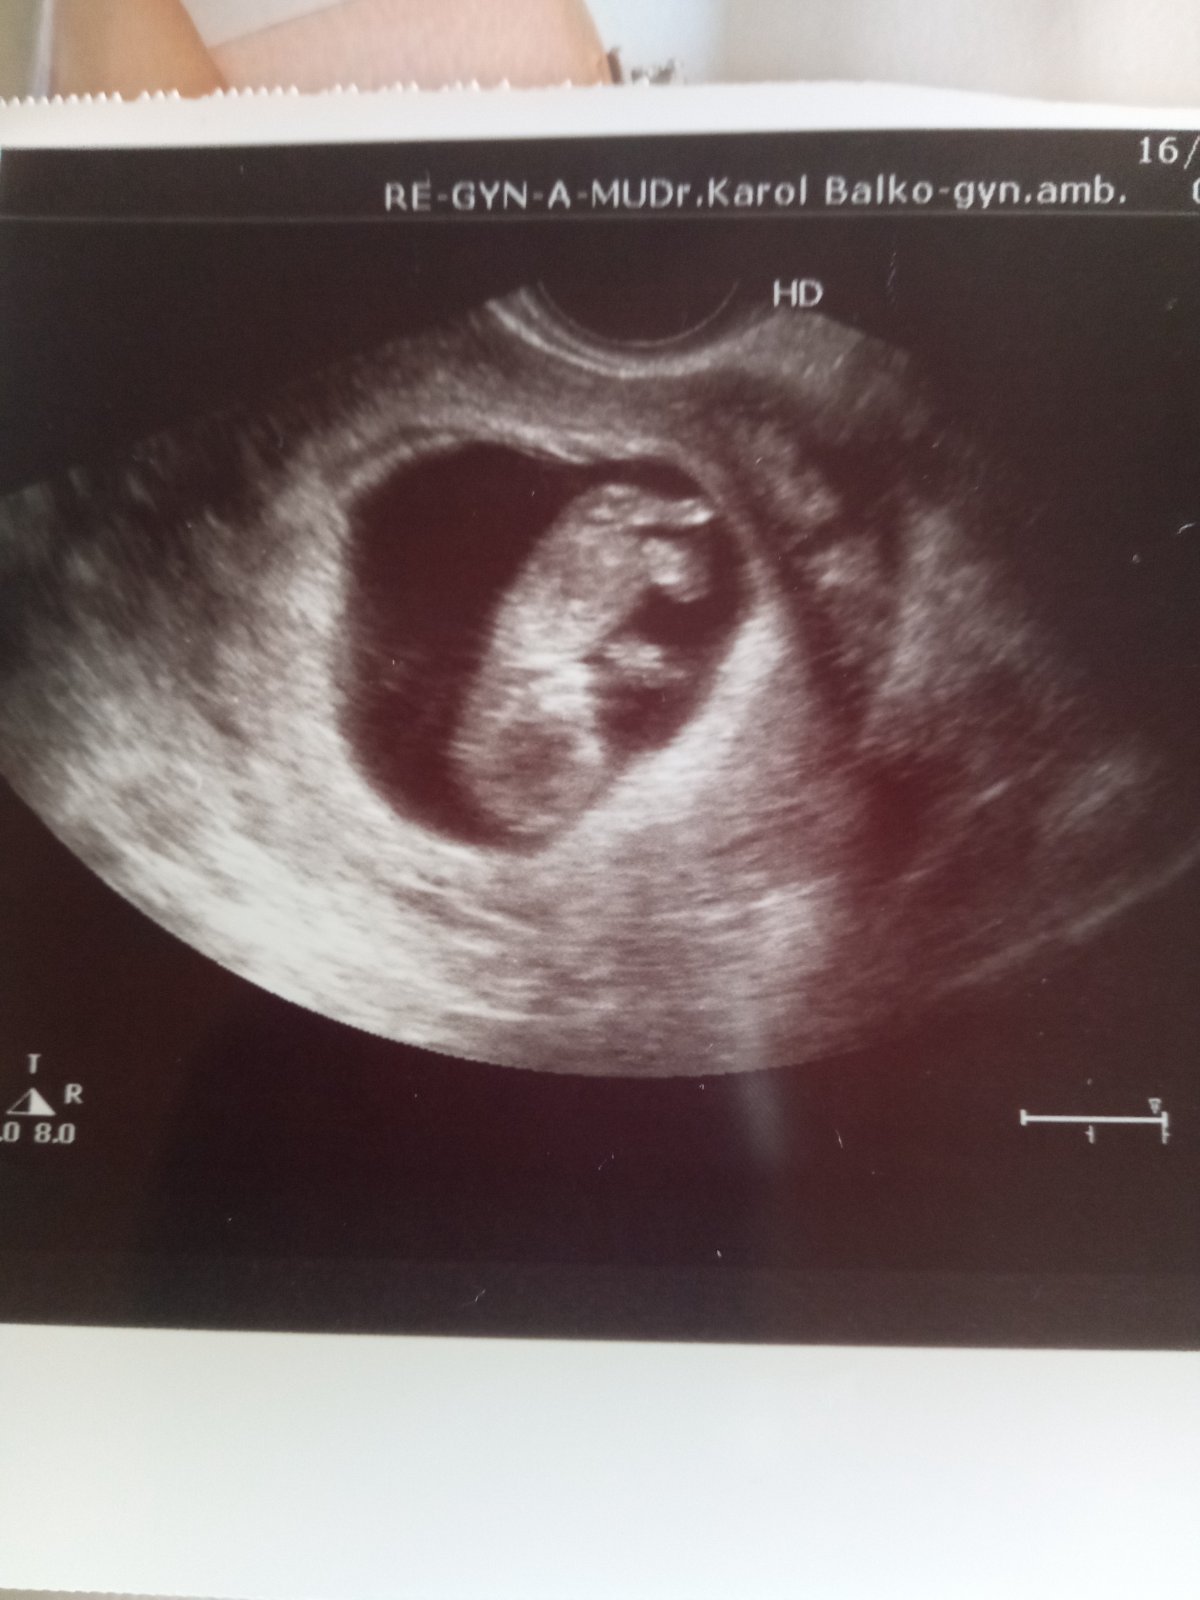

@sunny_g 11tt 😉

tak dvojicky to nebudu..aspon zatial teda sa ukazalo len jedno..ale hlavne,ze bude zdrave,to je dolezite 🙏